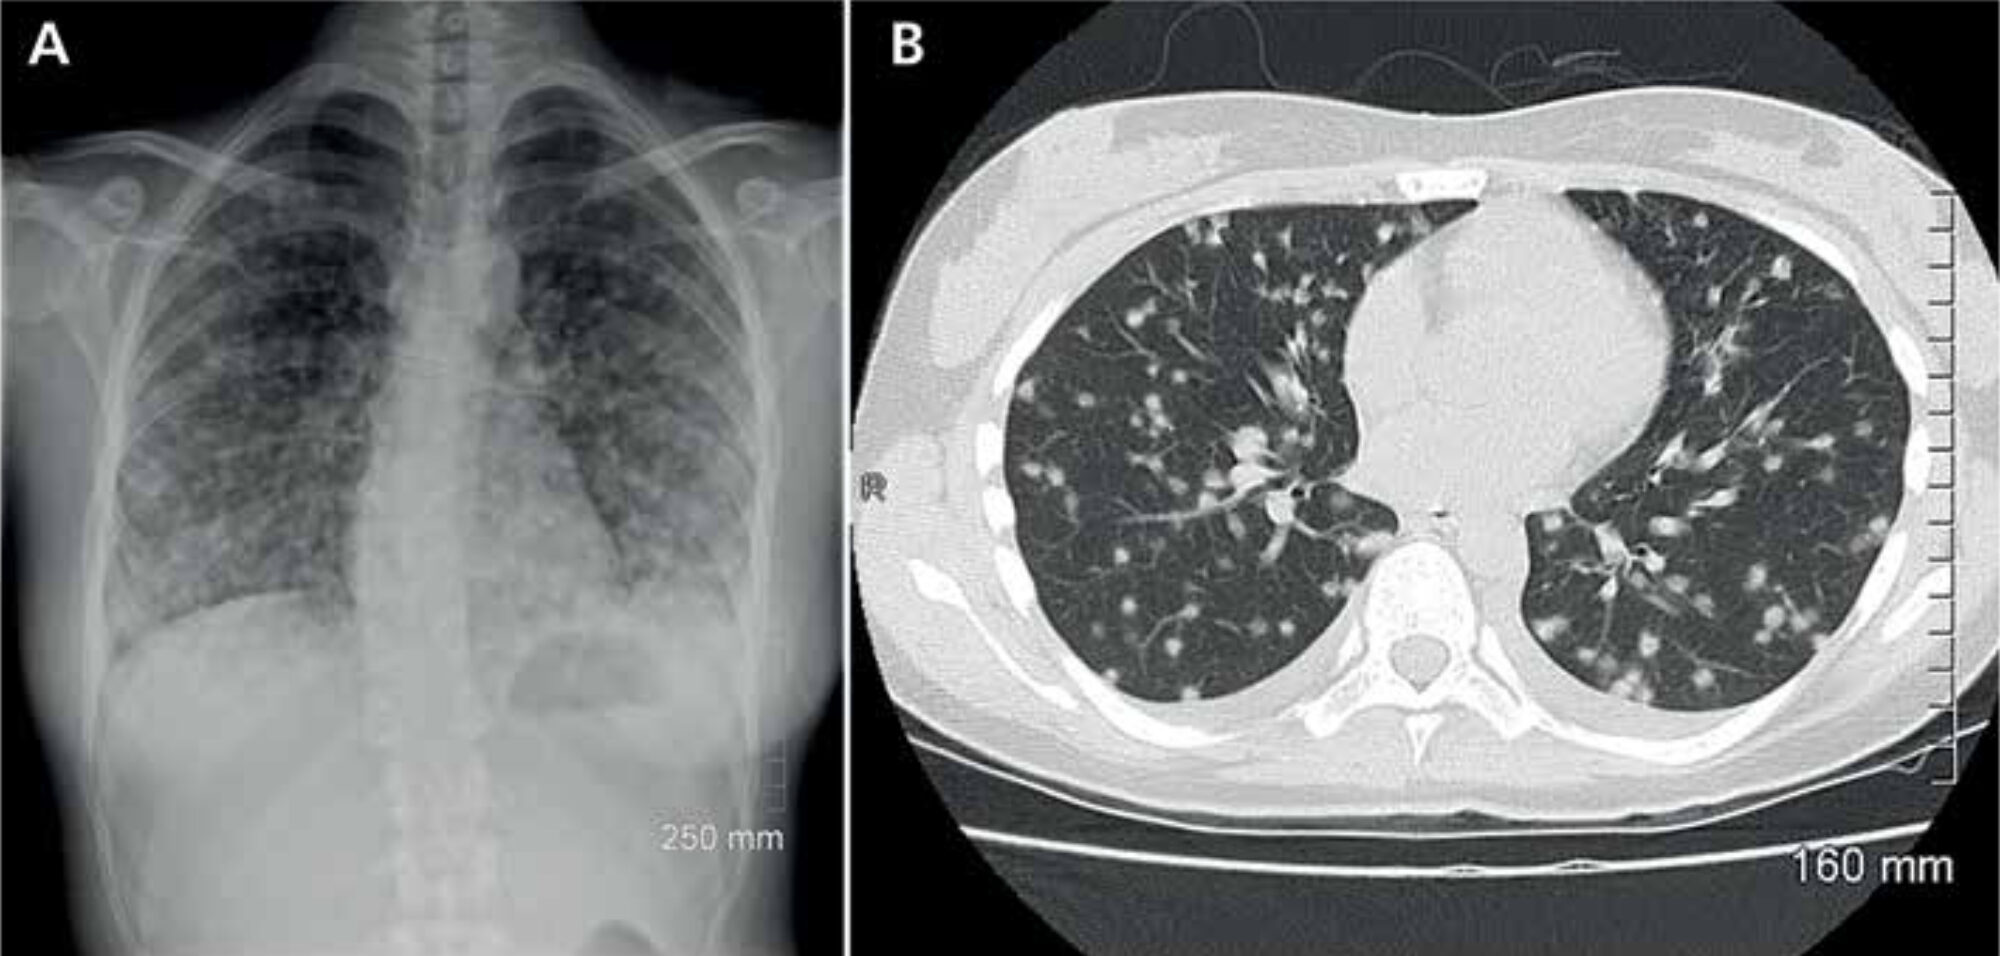

In most patients, infection is asymp-tomatic, but it may lead to disseminated histoplasmosis, a life-threatening ill-ness. Upon infection, patients usually present themselves with pulmonary complaints (Figure 2). A more general presentation with malaise, fever, myal-gia, rheumatic manifestations or even central nervous system histoplasmosis may occur. Diagnosis is confirmed by a positive culture or, more rapidly, by antibody or antigen testing.[6] Because histoplasmosis is known to mimic other diseases, the risk of exposure is an important clue to raise the index of suspicion. The recently published systematic review by Antinori et al. described that progressive dissemina-tion was mostly seen in HIV positive patients, but that the worst outcomes were seen in HIV negative immuno-compromised subjects, with a mortality rate of 32%.[5] Treatment options include intravenous amphotericin B or oral itraconazole. The latter is recommended by the Infectious Diseases Society of America as prophylactic therapy in HIV positive patients in highly endemic areas. The duration of treatment depends on the severity of the disease.